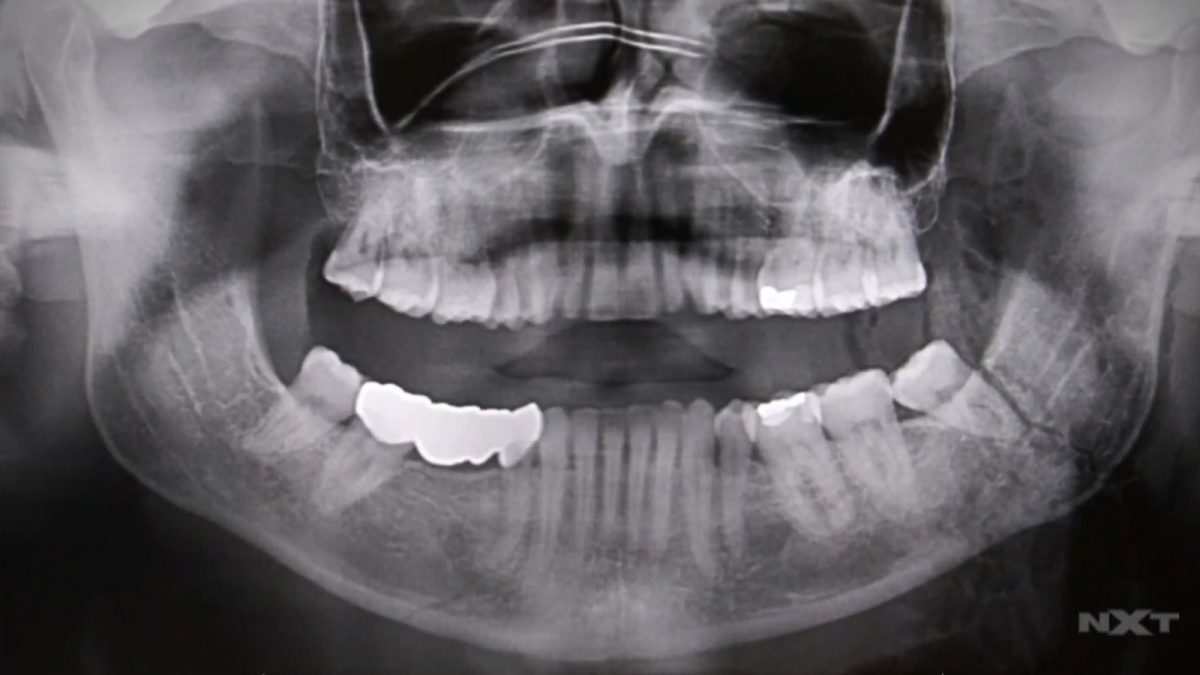

Finn Balor revealed that he has a “broken jaw in two places” following his NXT Championship match against Kyle O’Reilly at TakeOver on Sunday.

Broken jaw in two places.

Triple H said that Balor was getting x-rays after the match and a broken jaw was feared. The injury appears to have happened when Kyle O’Reilly hit him with a high knee to the face.

“Finn had two fractures in his jaw,” WWE ringside physician Dr. Jeffrey Westerfield said in the segment. “Once the swelling goes down in a couple of days, Finn’s gonna be able to talk very sparingly. Obviously, it’s gonna have him out for a little bit of time.”